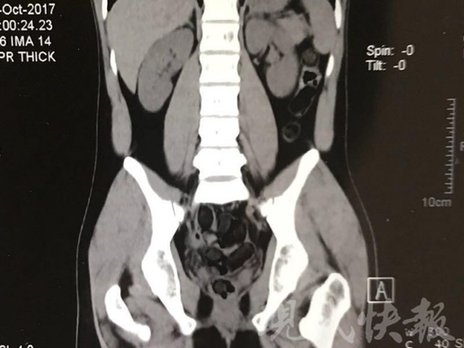

小伙體內(nèi)藏毒300余克 CT掃描圖密密麻麻

運(yùn)毒小伙:希望被判處死刑

由于毒品在體內(nèi)一旦泄露有可能致命,警方第一時(shí)間將阿永帶到醫(yī)院進(jìn)行檢查。CT 掃描的結(jié)果顯示,阿永體內(nèi)布滿了密密麻麻的白色圓柱狀固體,就像一粒粒的蠶蛹。在南京市公安局鼓樓分局二板橋派出所,阿永分四次排出了毒品,毛重369.99克。經(jīng)訊問,阿永交代了自己全部的犯罪事實(shí)。目前,阿永已被刑事拘留。